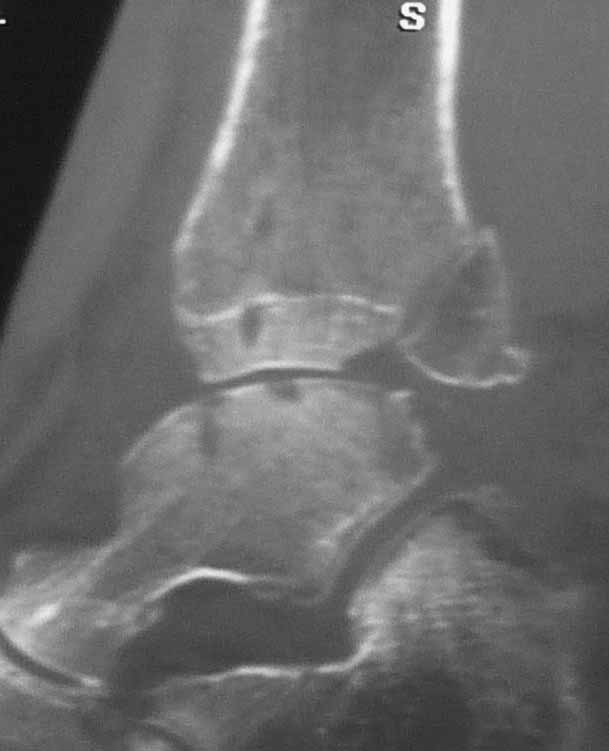

Уважаемые коллеги. Не так давно на форуме коротко обсуждались возможные последствия трансартикулярной фиксации голеностопного сустава при переломовывихах лодыжек.

На днях довелось увидеть КТ после удаления спиц. Картинки наглядные и, практически, не нуждаются в комментариях. Одна из спиц, кстати, проходила через фрагмент заднего края.

Картинки наглядные и, практически, не нуждаются в комментариях. Одна из спиц, кстати, проходила через фрагмент заднего края

Снимки являются доказательством важности защиты суставного хряща от грубой интервенции, и особенно от тех неудачных многочисленных попыток фиксации спицами, когда спицы оставляют на поверхности сустава непоправимые следы. Понятно, что повреждение целости хряща приводит к развитию хондролизиса, артрозу и т.д....

Но прежде, чем давать окончательную оценку, надо разобраться, почему была выбрана трансартикулярная фиксация. И применение транс-артикулярной фиксации можно оправдать, когда метод применяется временно ради спасения всего сустава, или когда ситуация не позволяет провести традиционную фиксацию. Тогда можно пойти на жертву, т.е. на повреждения небольшого участка хряща.

Понятно, огромные “дырки” в суставе не от хорошей жизни, хотя на самом деле “увеличенная картина” на КТ срезах может оказаться банальным проколом от 1,2 или 2 мм спиц. Большие неприятности, когда спицы находятся долго, и когда лизис вокруг спицы принимает большие размеры. А так - не стал бы драматизировать единичные спицы, установленные на короткое время, потому что такие “интервенции” сустава у большинства больных проходят без клинических проявлений.